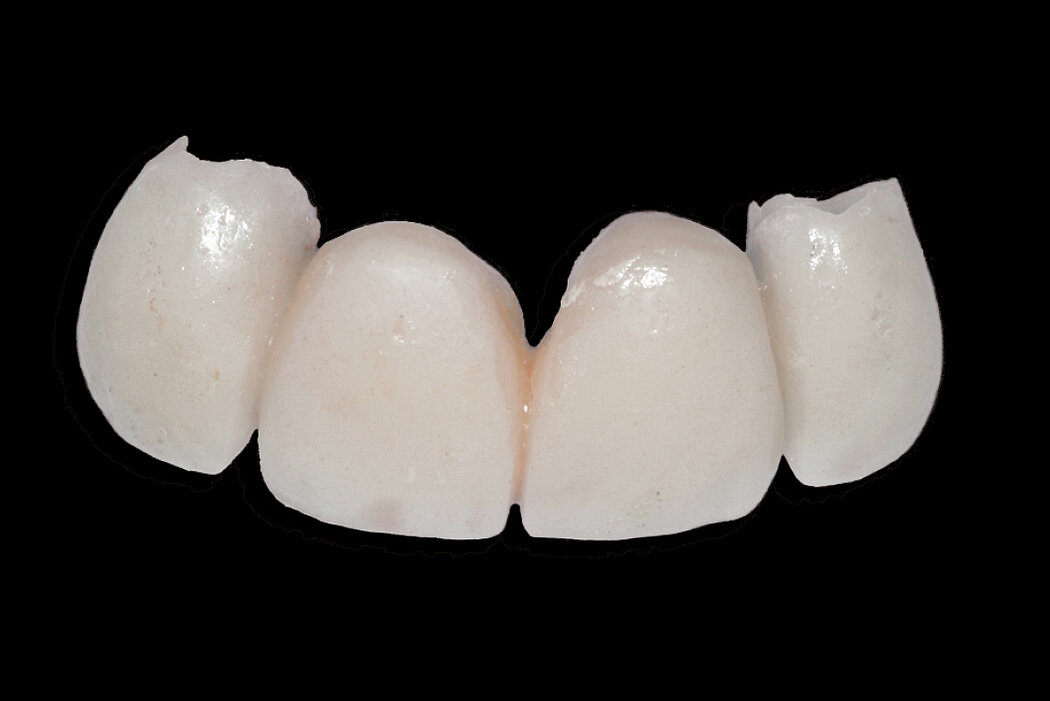

Bridge Restoration

When placing a prosthetic bridge after tooth extraction, Ridge Preservation with Geistlich biomaterials helps to preserve the bone volume and achieve optimal soft tissue esthetics under the pontic.1